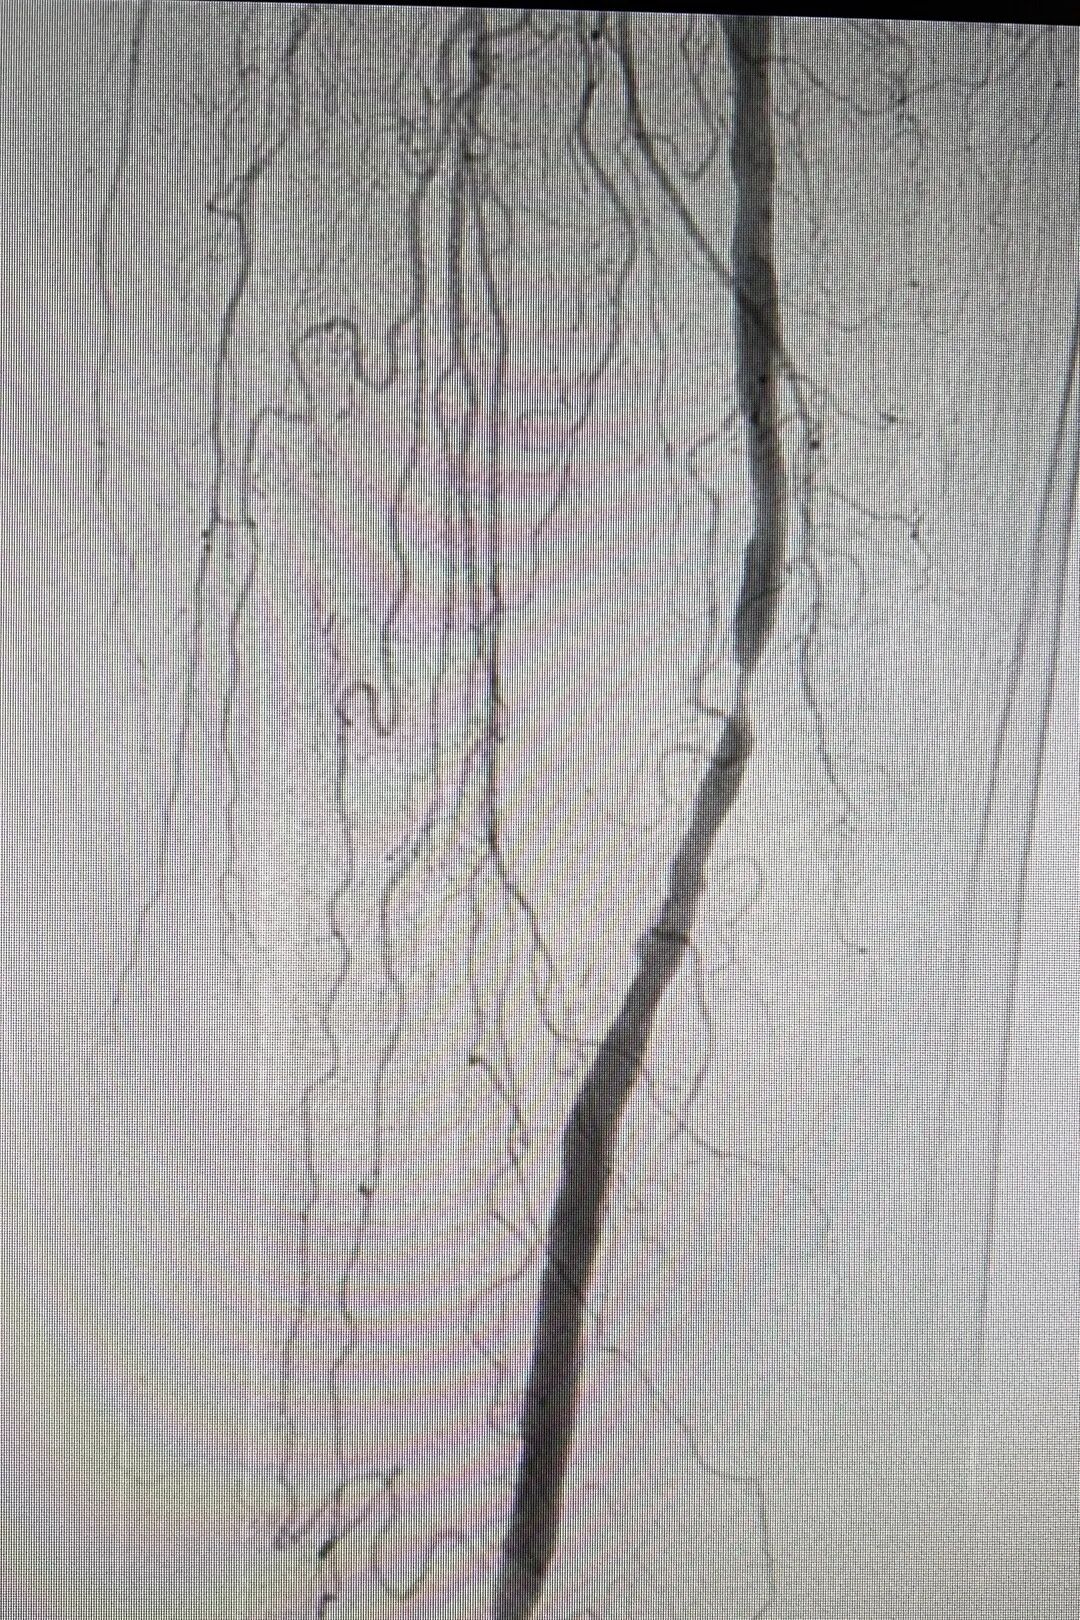

四肢血管系统

DSA 技术可诊断躯干各动脉以及分支的阻塞和狭窄,可以精准地诊断患者的动脉瘤以及各种动脉的畸形。